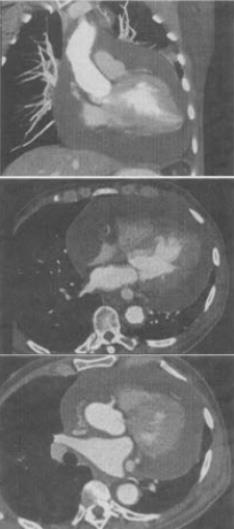

- 单项选择题 患者男,28岁,胸闷气急,伴干咳,查体见劲静脉显露,CT如图,最可能的诊断为()。

- B